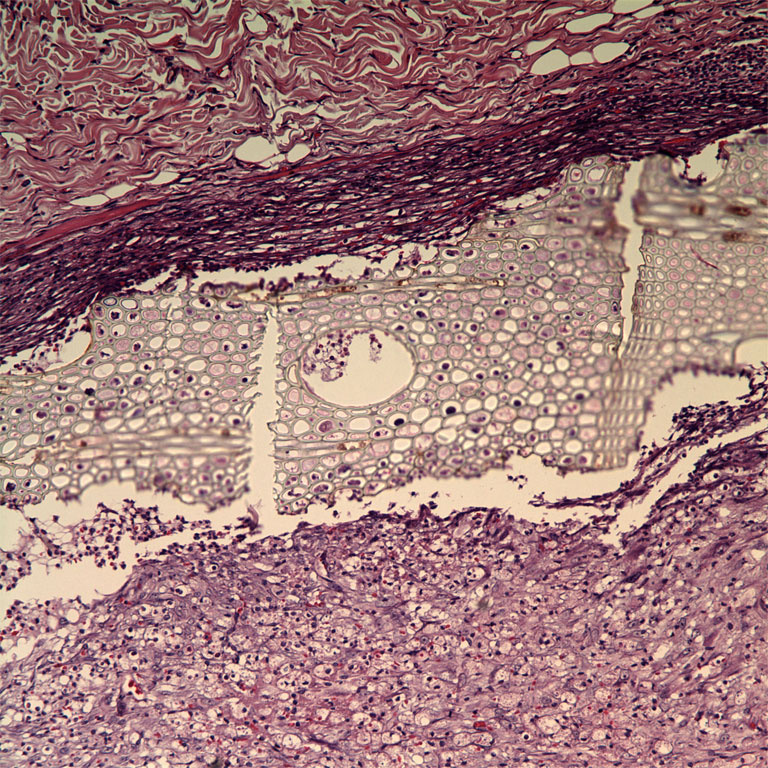

"This image shows histological findings in rats injected with a new tissue-glue (often called tissue adhesive), shown in the center between the two opposite sides of the glued tissue. We wanted to learn tissue reaction to the new formula synthesized in our lab. For surgical adhesives to be attractive alternatives to sutures and staples they should allow rapid adhesion and maintain strong and close apposition of wound edges for a sufficient time. This glue elicited a 'mild' histological response, which was characterized by inflammation surrounding the implanted material."